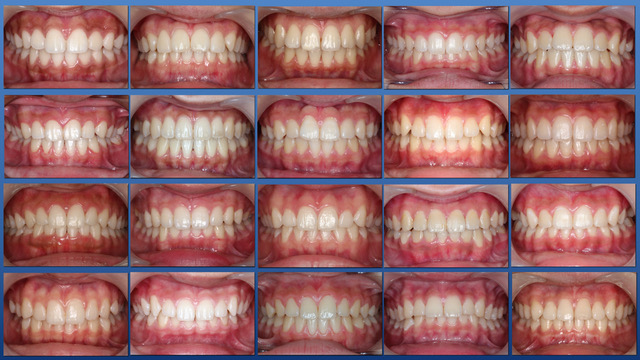

定期健診を継続し、虫歯に一回もなったことのない歯並びのきれいな患者さんが多く育っています。

子供達を健康で綺麗な歯並びの永久歯列に誘導していくことを咬合育成と言います。開業時から来院していた子供達を見ていて、どうしたら綺麗な歯並びにできるのかを研究してきました。最近その成果が上がるようになり多くの子供達が健康できれいな歯並びをもった大人になって来院するようになっています。対外的にも「講演・論文」のページにあるように各地の歯科大学や歯科医師会からその分野の講演を依頼されるようになり、いつのまにか須貝歯科医院の得意分野になってしまいました。永久歯への生え替わりの時期が最も重要な時期です。簡単な装置で歯並びを改善していくのですが患者さんによっては矯正専門医に紹介しなければならないケースもあります。その時は地元の信頼できる矯正専門医をご紹介しています。

上の前歯は下の前歯より前にないといけませんが、前歯の生え替わりの時に1本逆に生えてきました。そのままではきれいな歯並びにはなりそうもありません。この時が治療のタイミングです。簡単な矯正装置で改善しただけでその後きれいな永久歯列になりました。

須貝歯科医院では小児の患者さんに咬合育成を行っていますが矯正歯科医院ではありません。小さい頃からお口の管理をすることできれいな歯並びと虫歯のない健康なお口にすることを目標にしています。矯正治療のみのご希望はお受けしておりません。